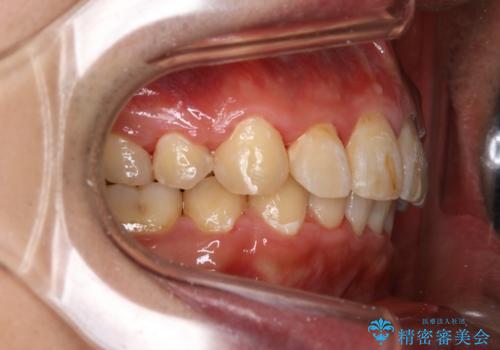

- 上顎前歯の突出感と下顎前歯のガタつきが主訴で来院されました。

出っ歯とガタつきの改善を行うには抜歯が必要と診断し、上下左右第一小臼歯を抜歯する計画を立てました。

抜歯する事で歯の移動量が大きいことからワイヤー表側矯正装置で治療を行うことになりました。